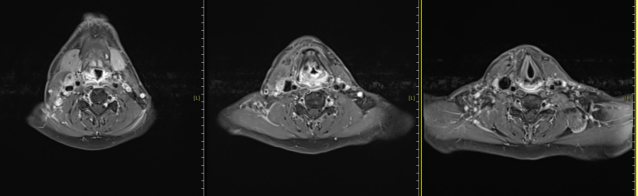

The patient was admitted to our hospital on January 7, 2025, and underwent multidisciplinary consultation before receiving carbon ion therapy for hypopharyngeal malignant tumor on January 16, 2025. The prescribed doses were as follows: PTVp: 68Gy (RBE) / 17Fx, PTVnd-L: D95% = 64Gy (RBE) / 16Fx, PTVR: 60Gy / 15Fx, PTVL: 56Gy (RBE) / 14Fx. Concurrently, cisplatin monotherapy combined with nimotuzumab injection for targeted therapy was administered. A follow-up neck MRI showed a reduction in the primary lesion and bilateral neck lymph nodes compared to pre-treatment, with a recent evaluation indicating a partial response (PR).

MRI after carbon ion therapy